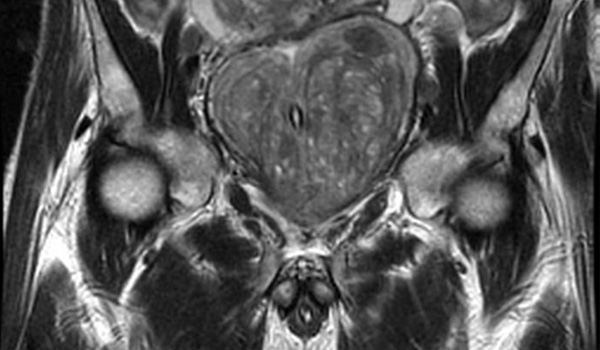

Los resultados de esta revisión sistemática y metanálisis sugieren que la integración de la resonancia magnética en las vías de detección del cáncer de próstata se asocia con un número reducido de biopsias innecesarias y un sobrediagnóstico de cáncer de próstata insignificante, al tiempo que se mantiene la detección de cáncer de próstata clínicamente significativo en comparación con la detección solo con PSA. JAMA Oncol,  5 de abril de 2024

Los resultados de esta revisión sistemática y metanálisis indican que la integración de la resonancia magnética (RM)  en las vías de cribado del cáncer de próstata (CaP) se asocia con un número reducido de biopsias innecesarias y un sobrediagnóstico del CaP insignificante, al tiempo que se mantiene la detección de CaP clínicamente significativos (csPCa)  en comparación con el cribado solo del PSA. JAMA Oncol 5 de abril de 2024